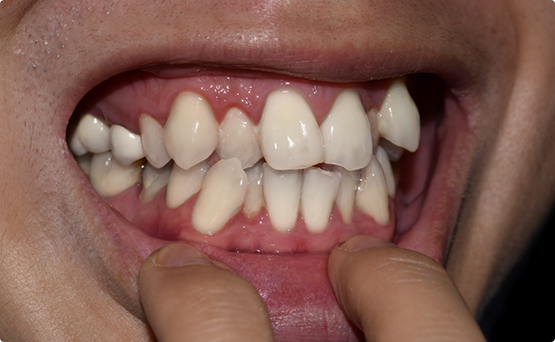

Case 2

Adult female, unilateral posterior crossbite, crowded upper arch, class II molar relation on the right with narrow smile on the right side.

Treatment: Patient was treated with an expander followed by Invisalign clear aligners.